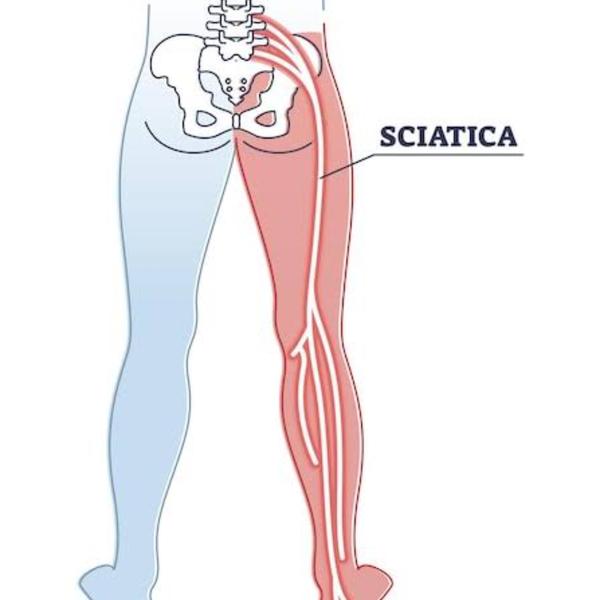

WHAT IS SCIATICA? Sciatica or sciatic pain radiat...